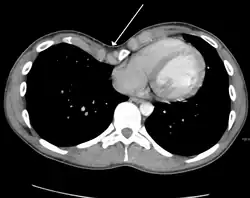

Axial CT image showing a large left sided mass that appears attached to the pleura.

Masses such as tumors can also cause compression and displacement of mediastinal structures. There are various mediastinal tumors, and they are classified by their location in the chest. Notable examples include germ cell tumors and lymphomas.[12] Teratomas are a class of germ cell tumors that arise in the chest due to failure of germ cell migration during development. They can expand to large sizes and cause hemoptysis and pleural effusion. Radiographic features of teratomas typically include fluid and fat but also muscle, teeth, and bones inside the mass.[13]